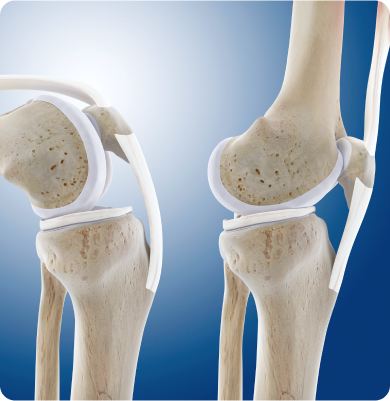

무릎 관절 내 충격을 흡수하는 반달 모양의 연골인 반월상연골이 찢어진 질환

무릎이 회전하거나 갑자기 꺾이는 움직임 중에 반월상연골에 무리가 가면서 손상이 발생하며 스포츠 외상이나 노화로 인한 연골의 퇴행성 변화로 발생합니다.